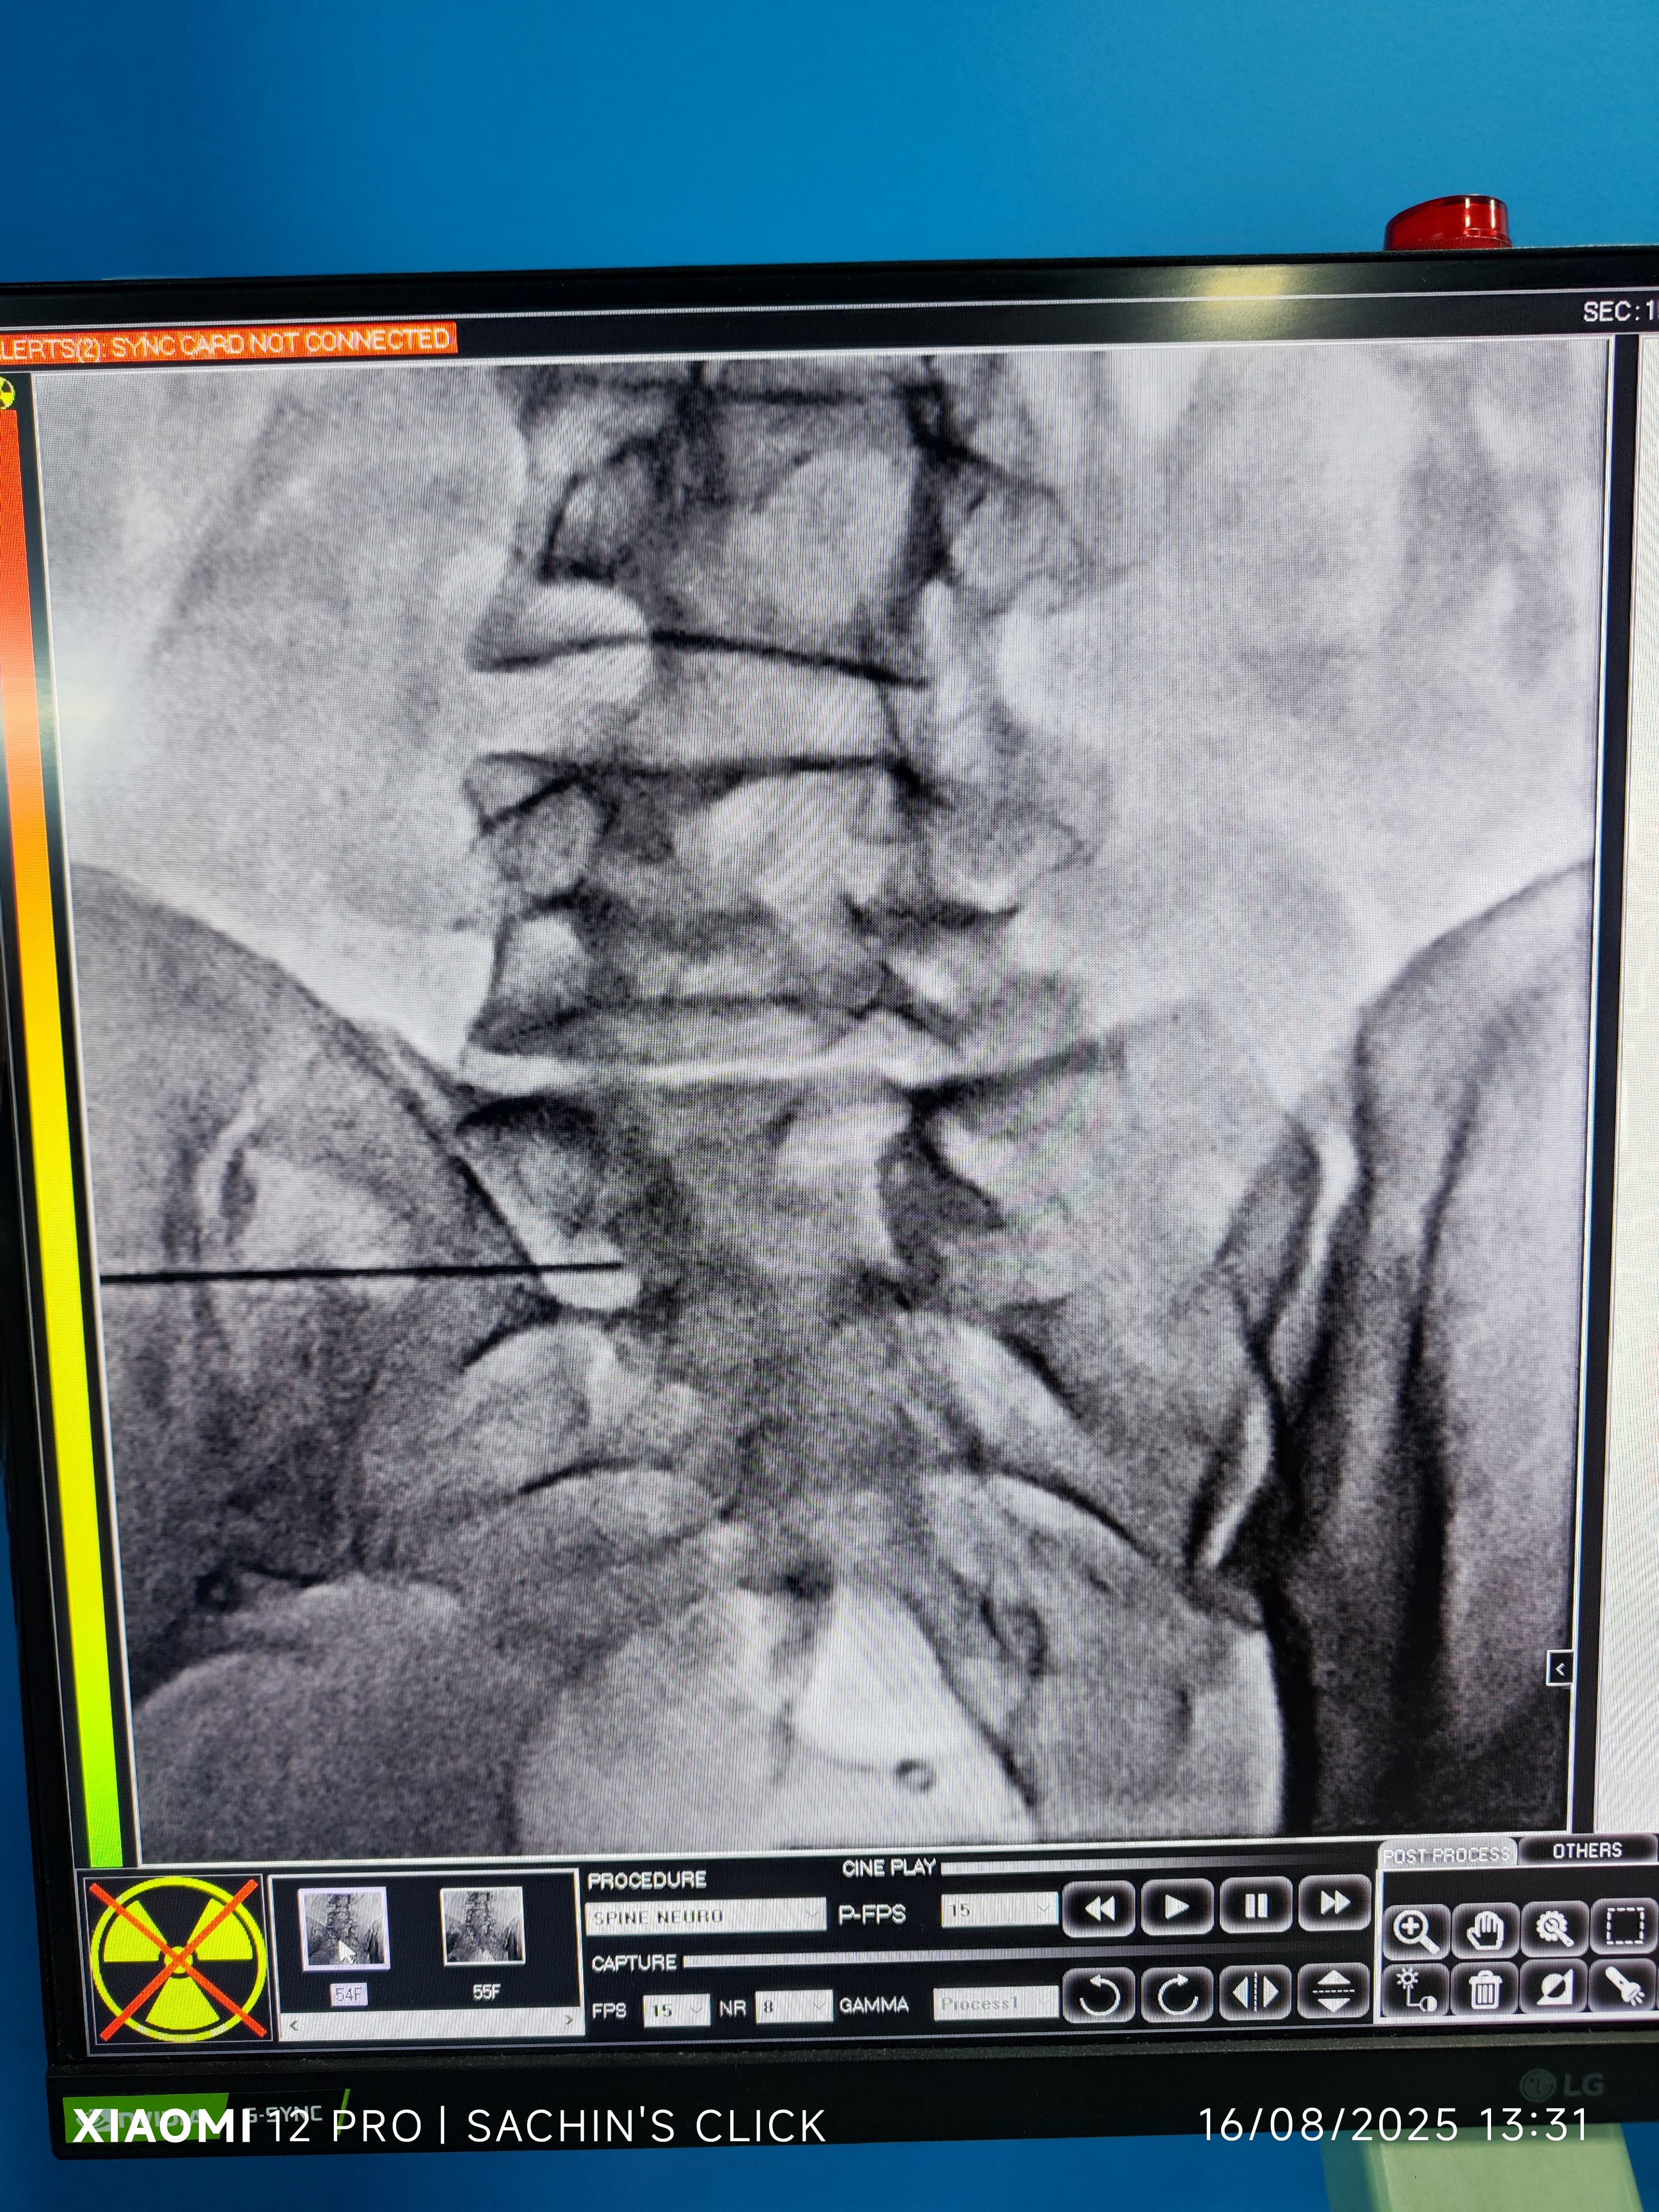

Glimpses of Advance Pain Care

Step inside our clinic and see our commitment to a healing environment and advanced care.